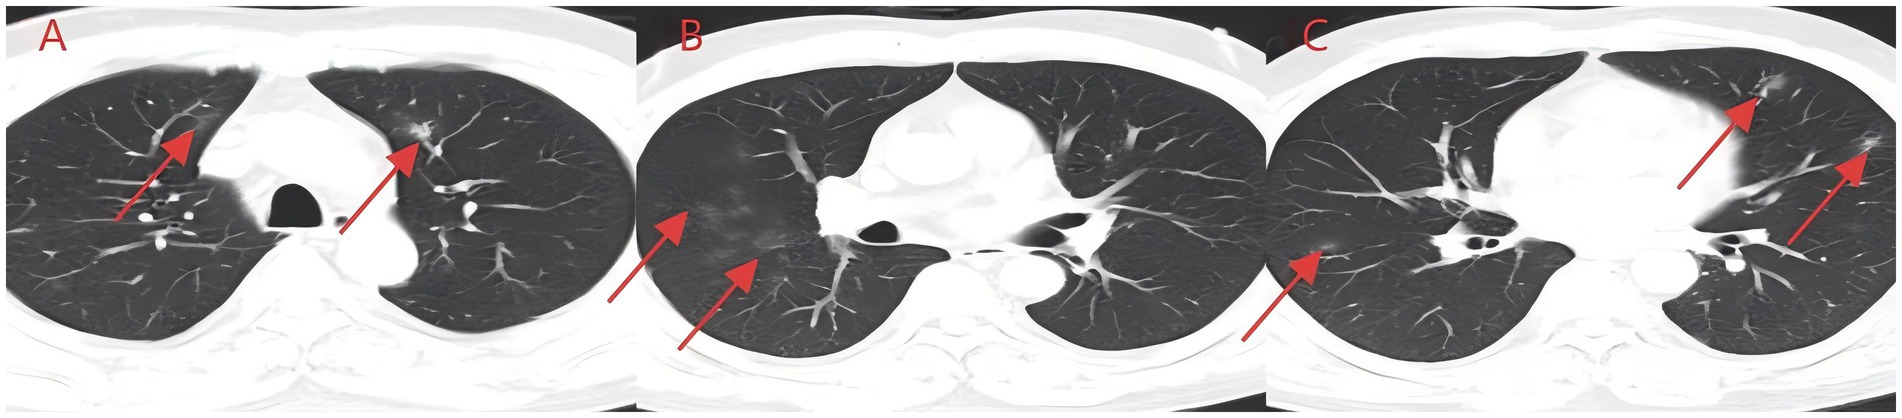

A middle-aged Asian man with a 2-day history of cough and expectoration was referred from the outpatient department to the Department of Respiratory Medicine. His symptoms started after exposure to chemical fumes at night and included a cough with expectoration secondary to pharyngeal irritation, as well as acid reflux and nausea. Due to the transient nature of the incident, it was not feasible to collect and analyze the irritating gas at the time. However, based on the patient’s description, it was inferred that they had inhaled substances similar to formaldehyde. Symptoms were more pronounced before bedtime and in the morning. The patient denied other systemic discomfort, and physical examination indicated no significant abnormalities. Standard laboratory tests were performed at admission, including a complete blood count, urinalysis, stool analysis, coagulation profile, tumor markers, respiratory virus screening, fungal (1–3)-β-D-glucan testing, and a Cryptococcus neoformans capsular antigen assay; none of these tests produced any significant findings. An external chest CT scan demonstrated bilateral ground-glass opacities (Figure 1). Due to a previous medical history of hypertension, at the time of admission, the patient was treated with irbesartan and oral hydrochlorothiazide. He denied having any additional long-term medical conditions or recognized food or drug allergies. To prevent potential bacterial infections, empirical antimicrobial therapy was started with 0.4 g of intravenous (IV) moxifloxacin once a day (qd). After ruling out any contraindications, an electronic bronchoscopy was performed, and alveolar lavage fluid samples were subjected to mNGS analysis. Bronchoscopic findings were normal, whereas mNGS identified T. whipplei with a sequence count of 372, and no other pathogenic microorganisms were detected. Therefore, the antimicrobial regimen was modified to IV ceftriaxone (CTX) 2 g/day in combination with oral sulfamethoxazole–trimethoprim (SMZ) twice daily for targeted infection control. After 6 days of treatment, the patient reported substantial improvement in cough and expectoration. However, despite medical advice, he refused a follow-up chest CT scan and additional inpatient care, opting to be discharged voluntarily. The patient showed no symptoms during the next phone follow-up.

Figure 1. (A–C) Aspiration of irritating gas chest CT (case 1). Asymmetric scattered ground-glass shadows were seen in both lungs, with no obvious solid shadows or pleural effusion.